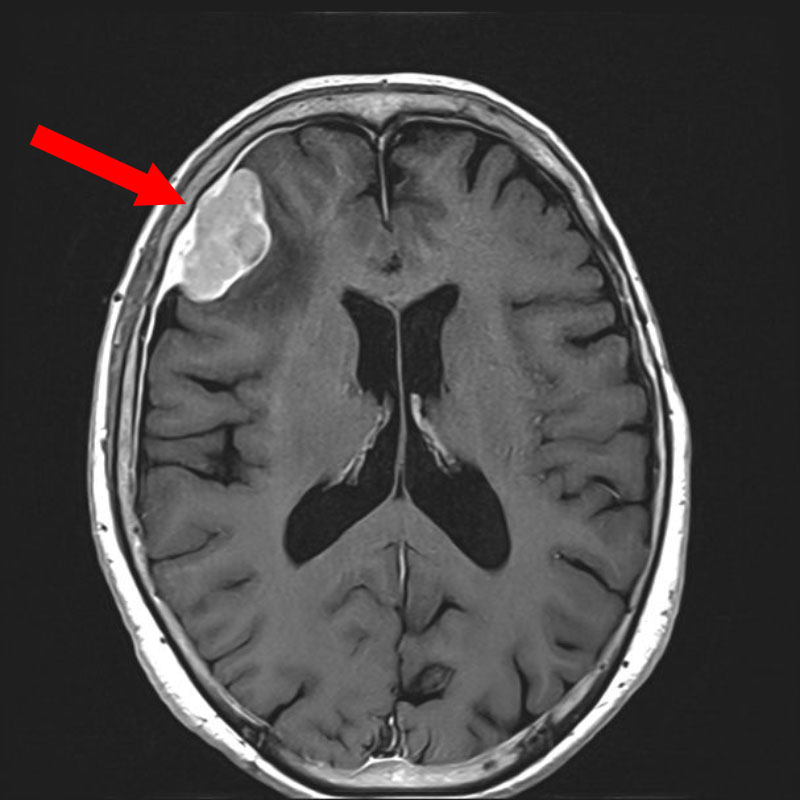

706

'25年12月

80代

右頭頂葉腫瘍

頭蓋内腫瘍摘出術

No.’25_108 手術前1

No.’25_108 手術前2